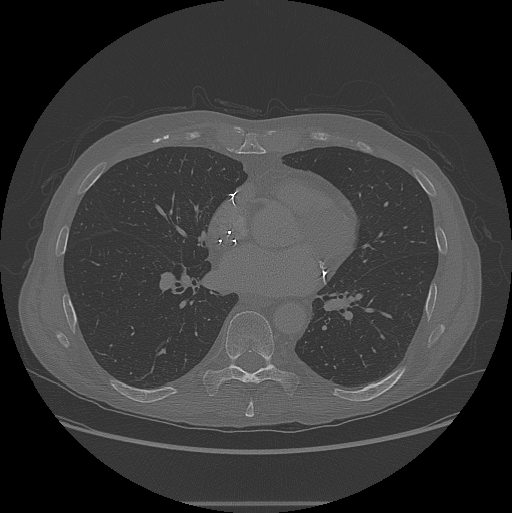

View the 2-D slices using the imshow function.

figure

imshow(XY,[],Border="tight")